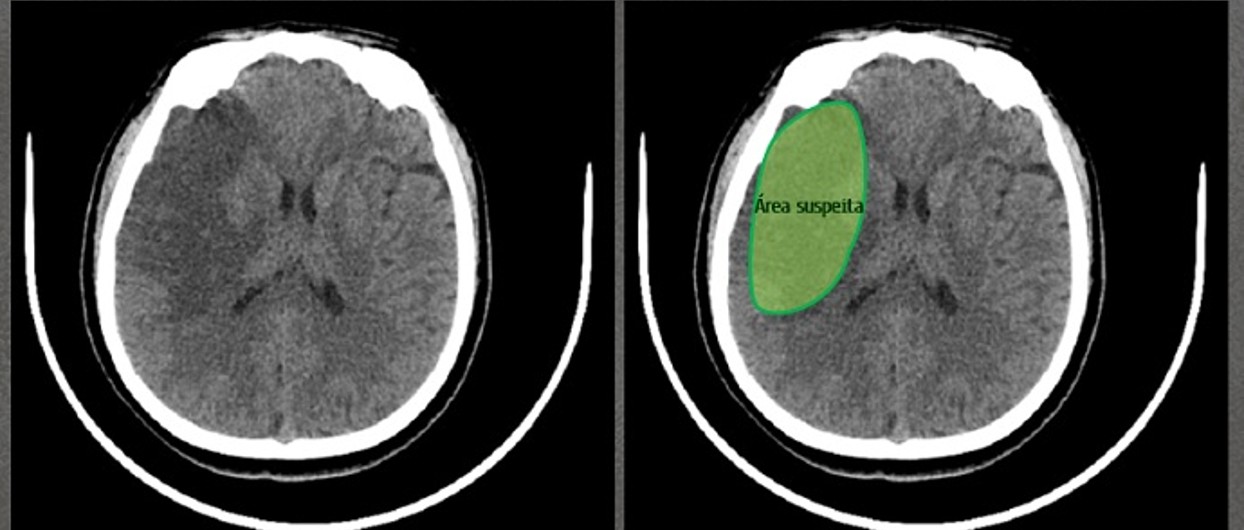

Apagamento do sulco cortical → perda da diferenciação entre giros e sulcos.

Perda da diferenciação entre substância cinzenta e branca → exemplo: apagamento do núcleo lentiforme.

Hipodensidade sutil em território vascular.